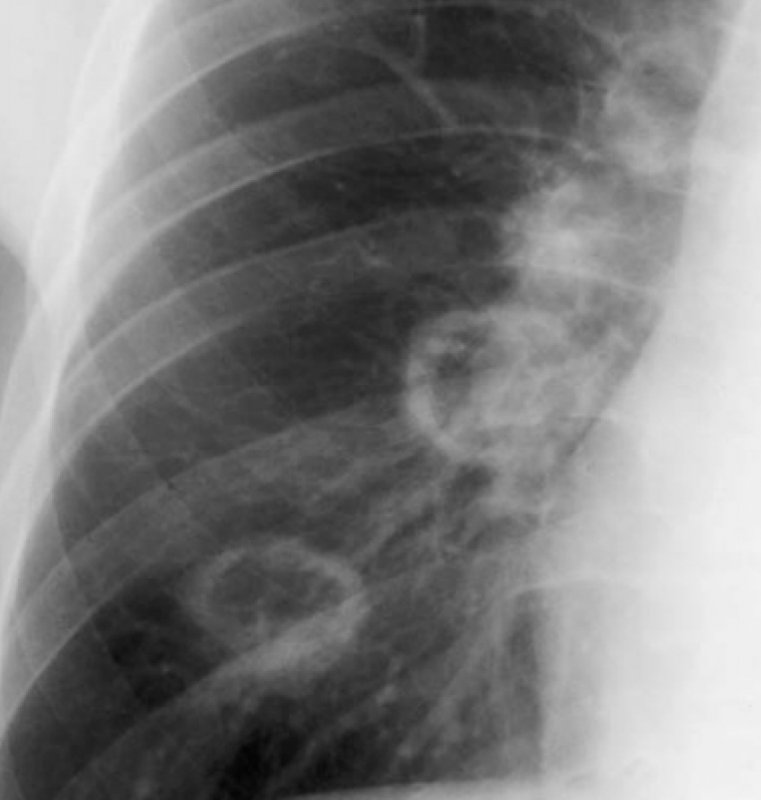

Гранулематоз Вегенера – системный некротизирующий васкулит, при котором происходит поражение верхних дыхательных путей с развитием изъязвлений (стоматит, трахеит, синусит, ринит), также возникает гломерулонефрит. На рентгенограмме легких могут обнаруживаться множественные инфильтраты неправильной округлой формы, размером до нескольких сантиметров. По мере развития заболевания в инфильтратах происходит распад – на их месте формируются тонкостенные полости (рисунок 2). При гранулематозе Вегенера могут возникать легочные кровотечения (на рентгенограмме в легких отмечаются инфильтративные изменения, как правило распространенные и двусторонние).

Рисунок 2. Гранулематоз Вегенера (увеличенный фрагмент рентгенограммы в прямой проекции – нижнее правое легочное поле). На фоне тени правого корня определяются 4 полостных образования в легком

Рисунок 6. Гранулематоз Вегенера. В обоих легких определяются множественные новообразования. В наиболее крупных образованиях видны полости с утолщенными стенками, а в образованиях среднего размера визуализируется уровень содержимого жидкость/газ